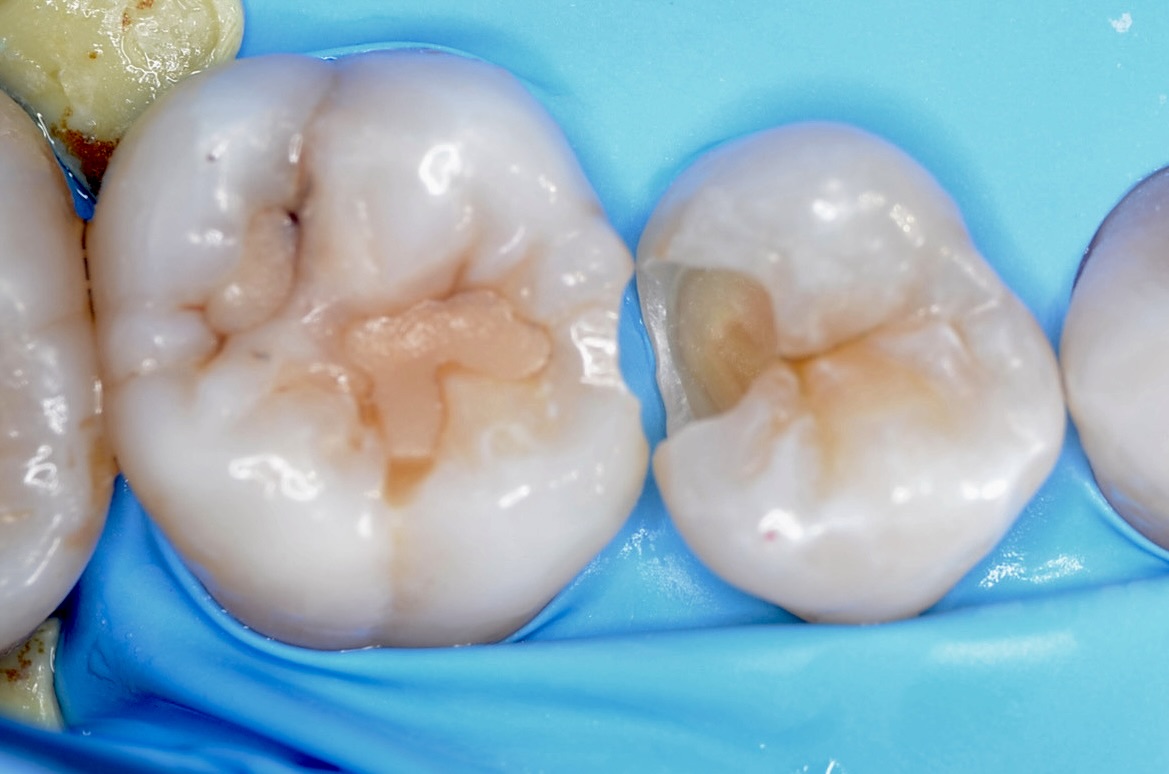

ラバーダム装着&歯間離開

虫歯治療においてもラバーダム装着は必須です。 唾液や血液から歯面が汚染されるのを防ぎ、乾燥状態を保つラバーダムは、接着力を向上させるためにも大切なアイテムです。 セパレーターという歯間離開器で強制的に歯間を1ミリほど広げて目視で虫歯の有無を確認します。 -

透照診

X線写真で確認はしていますが、歯と歯の間に虫歯があるかどうかを暗いところでライトを当ててチェックします。 -

少し歯を削る

虫歯のある部分を上記のチェックで確認した後、少しだけエナメル質を削ったところ、内部に虫歯が広がっているのを確認できました。 -